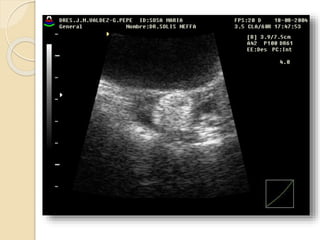

FIBROMA O LEIOMIOMA UTERINO

Patología común del útero que ocurre aproximadamente

en el 40% de las mujeres mayores de 35 años.

Los fibromas habitualmente son múltiples y más

comúnmente asintomáticos.

Se clasifican en:

• Submucosos: son los menos frecuentes pero es mas

probable que produzcan síntomas.

• Intramurales: Es el tipo mas común.

• Subserosos: Con frecuencia son pediculados y

pueden simular masas anexiales.